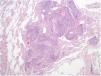

Due to symptoms’ persistence, with concomitant anorexia and loss of 10kg in 2 months, she was admitted into hospital for further evaluation. She denied smoking habits or occupational/environmental exposures. On examination she had a body mass index of 21kg/m2, pulmonary auscultation with subtle crackles in both lung bases, without arthritis, lymphadenopathies or organomegaly. Pulmonary function tests (PFTs), including carbon monoxide diffusing capacity (DLCO), were normal, without hypoxemia. Complementary exams showed negative viral serology (human immunodeficiency virus and hepatitis B/C), negative serology for acute infection by Mycoplasma pneumoniae, normal serum proteinogram, normal immunoglobulins levels and negative antinuclear antibodies. Abdominal/pelvic CT scan and endoscopy were normal. She was submitted to bronchoscopy with unspecific inflammatory changes; bronchoalveolar lavage had normal cellularity, without identification of any microorganisms, including Mycobacterium tuberculosis. Transbronchial biopsy had nonspecific lymphocytic infiltrate, forming small aggregates, without vasculitis, granulomas or neoplastic tissue. The patient was then submitted to surgical lung biopsy that demonstrated lymphoid follicles with peribronchiolar germinal centers and associated bronchiole constriction (Fig. 2), making the diagnosis of FB. The patient started PDN (0.75mg/kg/day), with clinical and radiological improvement, but one month later she developed steroid-associated neuropsychiatric symptoms and PDN was tapered. However, fever and sputum recurred, without evidence of infection. BF relapse was assumed and the addition of a second drug was discussed between rheumatologists and pulmonologists. Due to the absence of articular activity and considering the previous adverse events experienced by the patient with immunosuppressive drugs and the fear of these drugs to worsen lung disease, clarithromycin (500mg/day) was added for 4 months, with progressive symptomatic improvement and PDN tapering. Four months later complete resolution of chest CT alterations was noted (Fig. 1C, D) and PDN was stopped. The patient remains currently under no treatment for 10 months, without evidence of BF recurrence and no need for further immunosuppression.

PFTs can show a normal, restrictive or obstructive pattern,4,5 sometimes with reduced DLCO.5 The diagnosis is histological, consisting of hyperplasic lymphoid follicles with reactive germinal centers along small airways.5